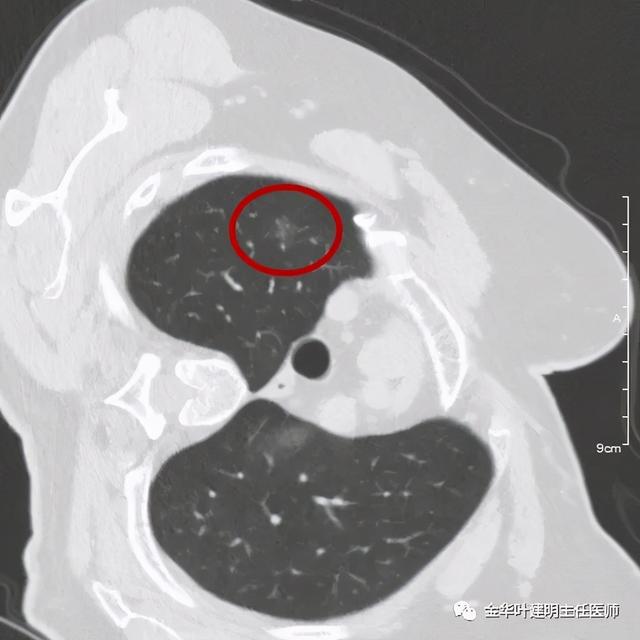

靶扫描更清楚显示瘤肺边界较清、分叶及密度不均杂乱 , 并有少许胸膜牵拉凹陷 , 当然考虑是肺癌 , 而且应该是浸润性腺癌了 。 其长径达2.5厘米!靶扫描还发现了平扫没被注意到的另一个病灶: